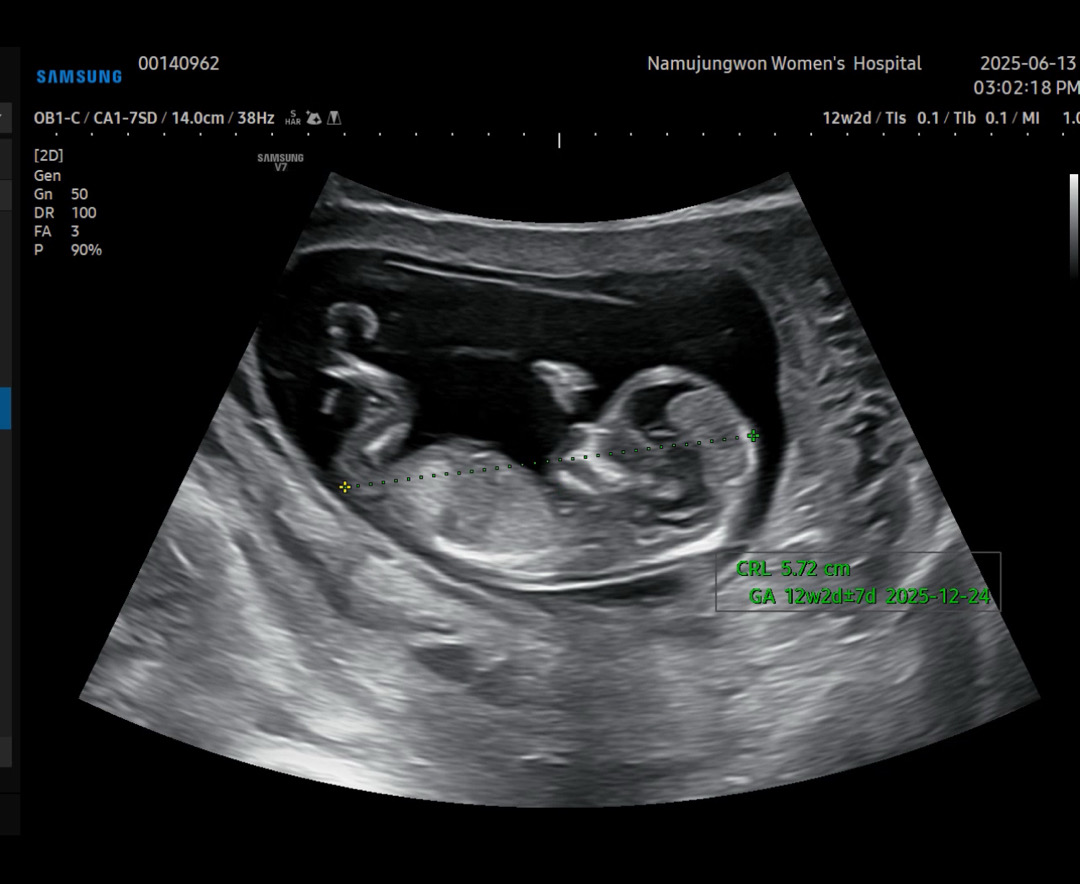

각도법 같이 봐주실수있을까요? 아들? 딸?

아들일까요 딸일까요???